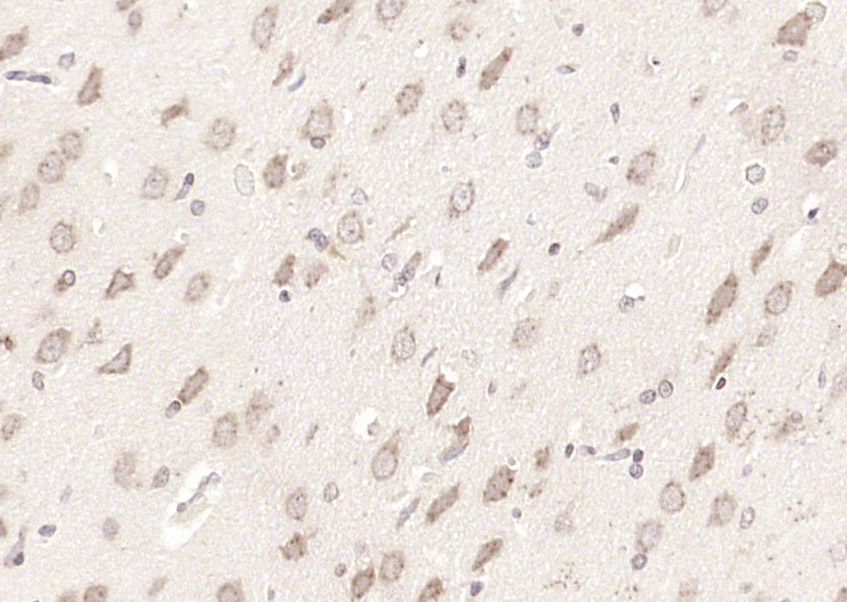

Paraformaldehyde-fixed, paraffin embedded (rat brain); Antigen retrieval by boiling in sodium citrate buffer (pH6.0) for 15min; Block endogenous peroxidase by 3% hydrogen peroxide for 20 minutes; Blocking buffer (normal goat serum) at 37°C for 30min; Antibody incubation with (NELL2) Polyclonal Antibody, Unconjugated (bs-11895R) at 1:200 overnight at 4°C, followed by operating according to SP Kit(Rabbit) (sp-0023) instructionsand DAB staining.

Paraformaldehyde-fixed, paraffin embedded (mouse brain); Antigen retrieval by boiling in sodium citrate buffer (pH6.0) for 15min; Block endogenous peroxidase by 3% hydrogen peroxide for 20 minutes; Blocking buffer (normal goat serum) at 37°C for 30min; Antibody incubation with (NELL2) Polyclonal Antibody, Unconjugated (bs-11895R) at 1:200 overnight at 4°C, followed by operating according to SP Kit(Rabbit) (sp-0023) instructionsand DAB staining.